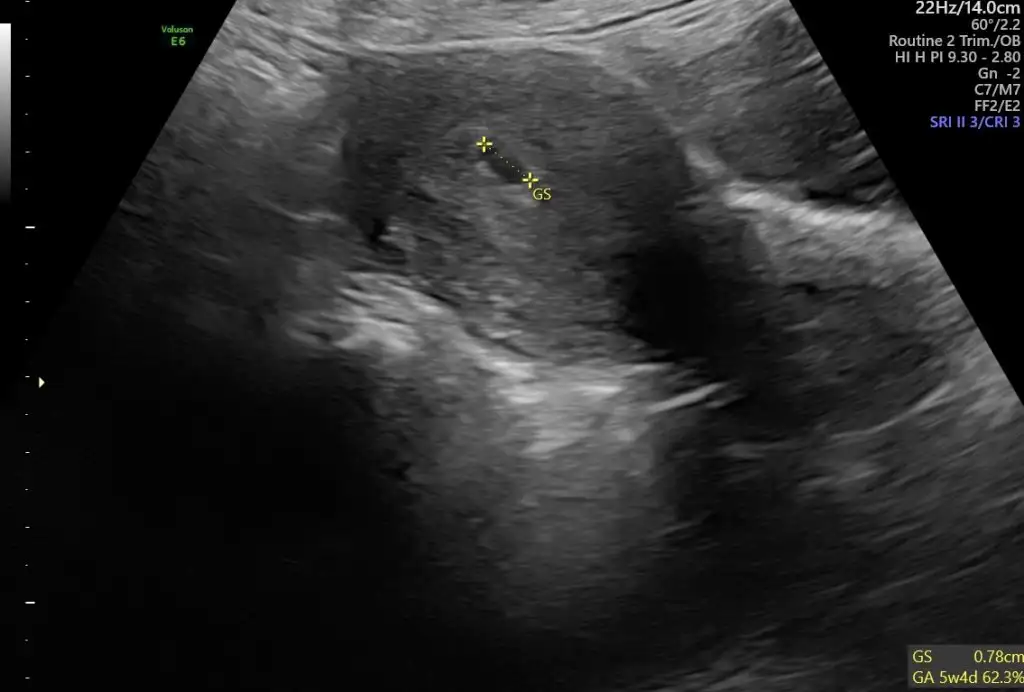

5., 6., ve 9+5 .haftaya ait karından ultrason görüntüleri :)Eki Görüntüle 3273013 Eki Görüntüle 3273014 Eki Görüntüle 3273015